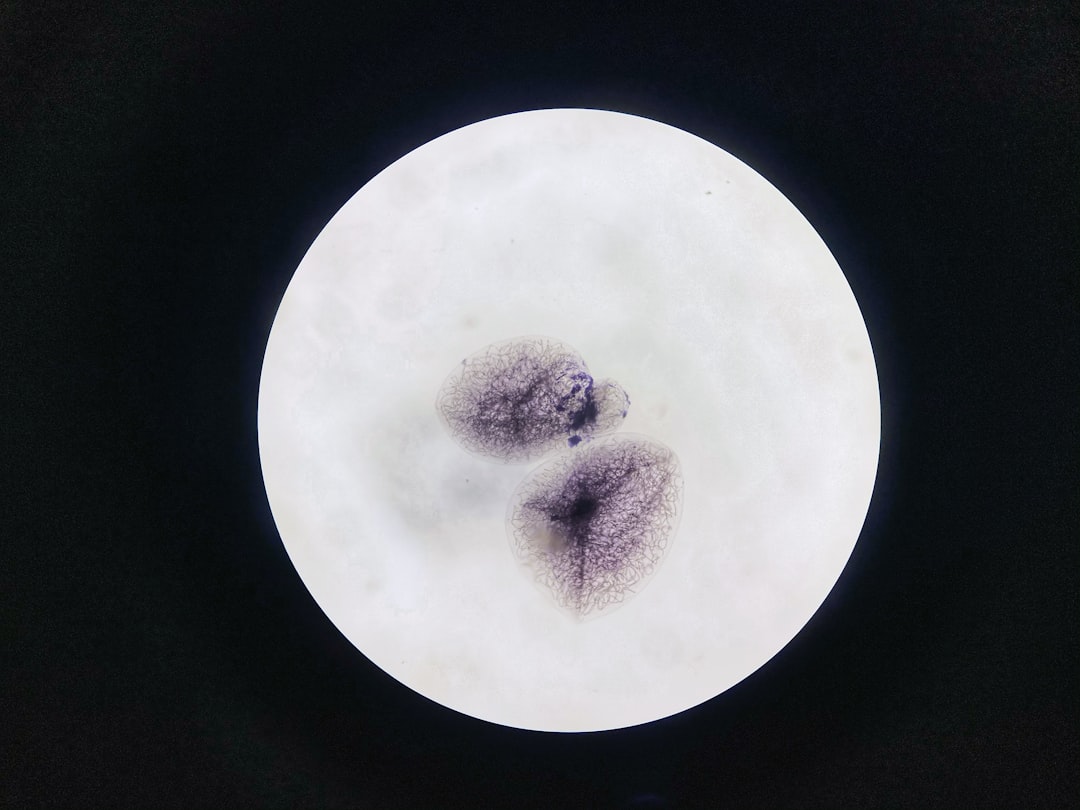

免疫細胞に侵入する寄生虫のイメージ

Photo by National Institute of Allergy and Infectious Diseases on Unsplash